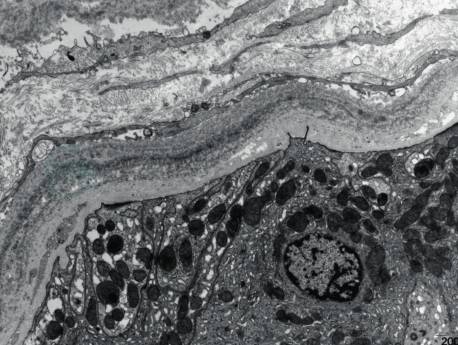

电镜检查可观察到LCDD特征性的超微结构改变,表现为细颗粒状电子致密物质沿肾小管基底膜外侧、肾小球毛细血管基底膜内侧、系膜区、Bowman囊壁及小血管壁沉积(图2、图3),具有重要诊断价值。疾病晚期,肾间质内亦可见类似颗粒状物质沉积。但是部分早期病例仅可观察到肾小球毛细血管基底膜内侧少量、节段性沉积的颗粒物质,此时尚需结合免疫荧光检查进一步确诊。

图3EM TBM外侧细颗粒状电子致密物

引自:肾脏病学.第4版.ISBN:978-7-117-30643-0.主编: